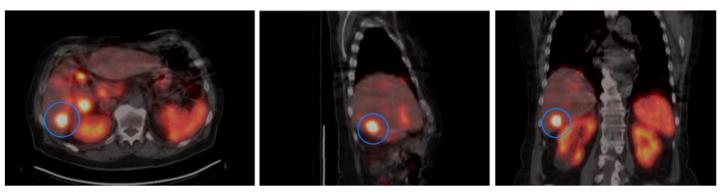

(1) Purpose: Small intestinal neuroendocrine tumors (SI-NETs) often present with distant metastases at diagnosis. Peptide receptor radionuclide therapy (PRRT) with radiolabeled somatostatin analogues is a systemic treatment that increases overall survival (OS) in SI-NET patients with stage IV disease. However, the treatment response after PRRT, which targets somatostatin receptor 2 (SSTR2), is variable and predictive factors have not been established. This exploratory study aims to evaluate if SSTR2 expression in SI-NETs could be used to predict OS after PRRT treatment. (2) Methods: Using a previously constructed Tissue Micro Array (TMA) we identified tissue samples from 42 patients that had received PRRT treatment during 2006-2017 at Sahlgrenska University hospital. Immunohistochemical expression of SSTR2, Ki-67 and neuroendocrine markers synaptophysin and Chromogranin A (CgA) were assessed. A retrospective estimation of Lu-DOTATATE uptake in 33 patients was performed. Data regarding OS and non-surgical treatment after PRRT were collected. Another subgroup of 34 patients with paired samples from 3 tumor sites (primary tumor, lymph node and liver metastases) was identified in the TMA. The SSTR2 expression was assessed in corresponding tissue samples ( = 102). (3) Results: The patients were grouped into Low SSTR2 or High SSTR2 groups based upon on levels of SSTR2 expression. There was no significant difference in Lu-DOTATATE uptake between the groups. The patients in the Low SSTR2 group had significantly longer OS after PRRT than the patients in the High SSTR2 group ( = 0.049). PRRT treated patients with low SSTR2 expression received less additional treatment compared with patients with high SSTR2 expression. SSTR2 expression did not vary between tumor sites but correlated within patients. (4) Conclusion: The results from the present study suggest that retrospective evaluation of SSTR2 expression in resected tumors cannot be used to predict OS after PRRT.

(1)目的:小肠神经内分泌肿瘤(SI-NETs)在诊断时常常已有远处转移。用放射性标记的生长抑素类似物进行肽受体放射性核素治疗(PRRT)是一种全身治疗方法,可提高IV期SI-NET患者的总生存期(OS)。然而,以生长抑素受体2(SSTR2)为靶点的PRRT治疗反应存在差异,且尚未确立预测因素。这项探索性研究旨在评估SI-NETs中SSTR2表达是否可用于预测PRRT治疗后的OS。(2)方法:利用先前构建的组织微阵列(TMA),我们从2006年至2017年期间在萨尔格伦斯卡大学医院接受PRRT治疗的42例患者中识别出组织样本。评估SSTR2、Ki-67以及神经内分泌标志物突触素和嗜铬粒蛋白A(CgA)的免疫组化表达。对33例患者进行了镥-奥曲肽摄取的回顾性评估。收集PRRT治疗后关于OS和非手术治疗的数据。在TMA中识别出另一组34例患者,其有来自3个肿瘤部位(原发肿瘤、淋巴结和肝转移灶)的配对样本。在相应的组织样本(n = 102)中评估SSTR2表达。(3)结果:根据SSTR2表达水平将患者分为低SSTR2组或高SSTR2组。两组之间镥-奥曲肽摄取无显著差异。低SSTR2组患者PRRT治疗后的OS显著长于高SSTR2组患者(P = 0.049)。与高SSTR2表达患者相比,低SSTR2表达的PRRT治疗患者接受的额外治疗较少。SSTR2表达在肿瘤部位之间无差异,但在患者体内具有相关性。(4)结论:本研究结果表明,对切除肿瘤中SSTR2表达的回顾性评估不能用于预测PRRT治疗后的OS。